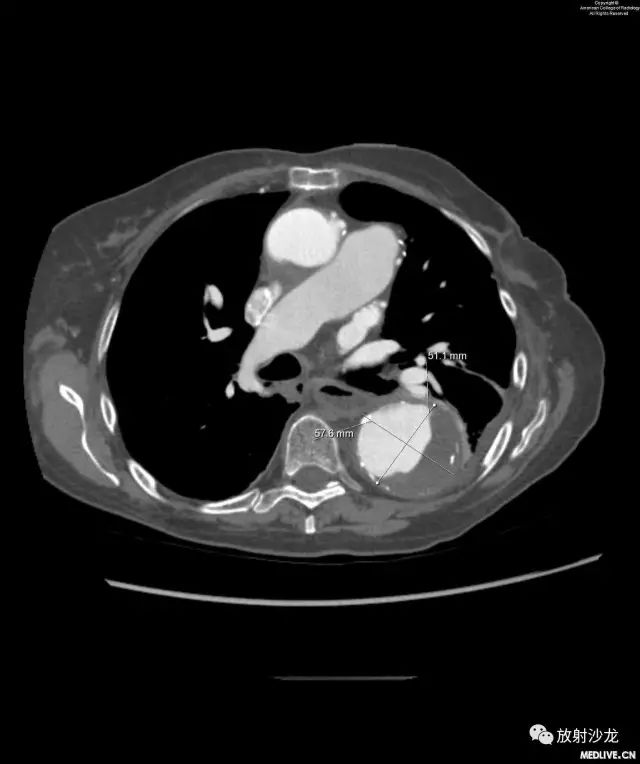

图7和图8:图7与图6为同一层面的图像。该患者恢复4周后再次出现新的胸痛。降主动脉扩张区可见假腔内血栓形成和慢性附壁斑块。图8与图6情况相似,额外补充了测量数据。